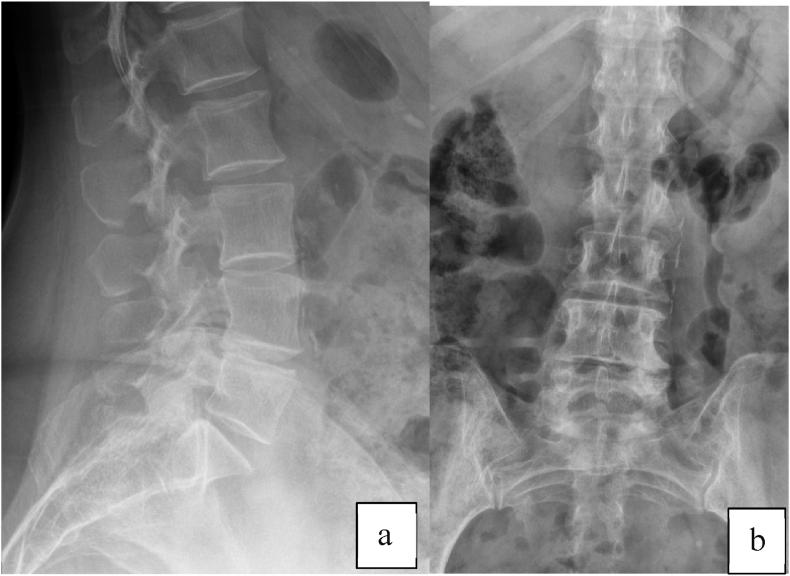

非典型腰椎椎弓根骨折。病例报告及文献比较综述:与双膦酸盐有关?可能符合股骨非典型骨折的诊断标准。

Atypical lumbar pedicle fractures. A case report and comparative review of the literature: Bisphosphonate-related? Possible matching with diagnostic criteria of atypical fractures of the femur.

In this paper we present a case of an atraumatic bilateral pedicle lumbar fracture, assuming the hypothesis of an insufficiency atypical fracture due to prolonged Alendronate therapy for osteoporosis. We highlight the various aspects for diagnosis, treatment and a review of the existing literature was carried out.

材料与方法

在本文中,我们报告了一例无创伤性双侧椎弓根腰椎骨折病例,假定其为因长期使用阿仑膦酸钠治疗骨质疏松而导致的非典型不全骨折。我们强调了诊断、治疗的各个方面,并对现有文献进行了综述。